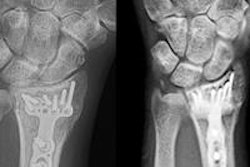

Biplane vs. single-plane imaging devices

One of the fundamental issues in the design of a hybrid OR suite is the choice for each room between biplane and single-plane imaging devices. If the projected case mix favors neuroendovascular procedures, biplane devices are desirable. However, the trade-off is a less effective setup for open procedures owing to the nature of the imaging table.

Currently, pedestal tables are not compatible with biplane devices, thus requiring surgeons to perform open techniques on an imaging table when biplanes are installed in hybrid operating rooms. On the other hand, if it is projected that only a limited number of neurological procedures will be performed in the suite (if any), a single-plane imaging device is a more appropriate selection from cost and operational efficiency standpoints.

Thanks in part to the development of faster and smaller microprocessors, the capabilities of both single and biplane devices have evolved rapidly in recent years. They now offer a host of axial imaging acquisition and postprocessing options with 3D imaging capability.4 Further, incorporation of robotics helps increase the flexibility in positioning these advanced imaging devices.

As more use of intraoperative axial imaging has become the standard of care in vascular practices, the consideration for more flexible C-arm positioning has become a critical factor in a hybrid suite. This is due to the nature of complex vascular hybrid procedures such as endovascular aneurysm repair (EVAR) and thoracic endovascular aortic/aneurysm repair (TEVAR), which may require various angles for image visualization and rotational angiography during the case.

Furthermore, having the ability to move the C-arm out of the surgical field for open cases and for a certain time during a hybrid procedure when no imaging is required enhances the intraoperative workflow and arguably patient safety. A C-arm mounted on a robotic arm with numerous pivoting joints allows for great flexibility in imaging the patient, superior axial imaging, and the ability to move the C-arm out of the way when not in use.

Given these considerations and our projected case mix, we decided that we should have two rooms each for biplane and single-plane devices: the biplane units primarily for the neuro work and the single-plane unit for abdominal, peripheral, EVAR, and TEVAR procedures.